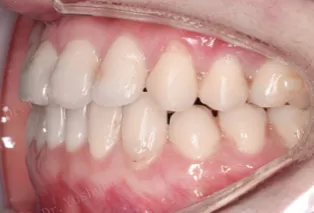

Intraoral photos after treatment

3. Two maxillary canines were congenitally missing, 3 were replaced by 4, and the occlusal relationship was adjusted from Class I relationship to completely Class II relationship.

4. Phase I to correct the corssbite and phase II to correct mandibular deviation.